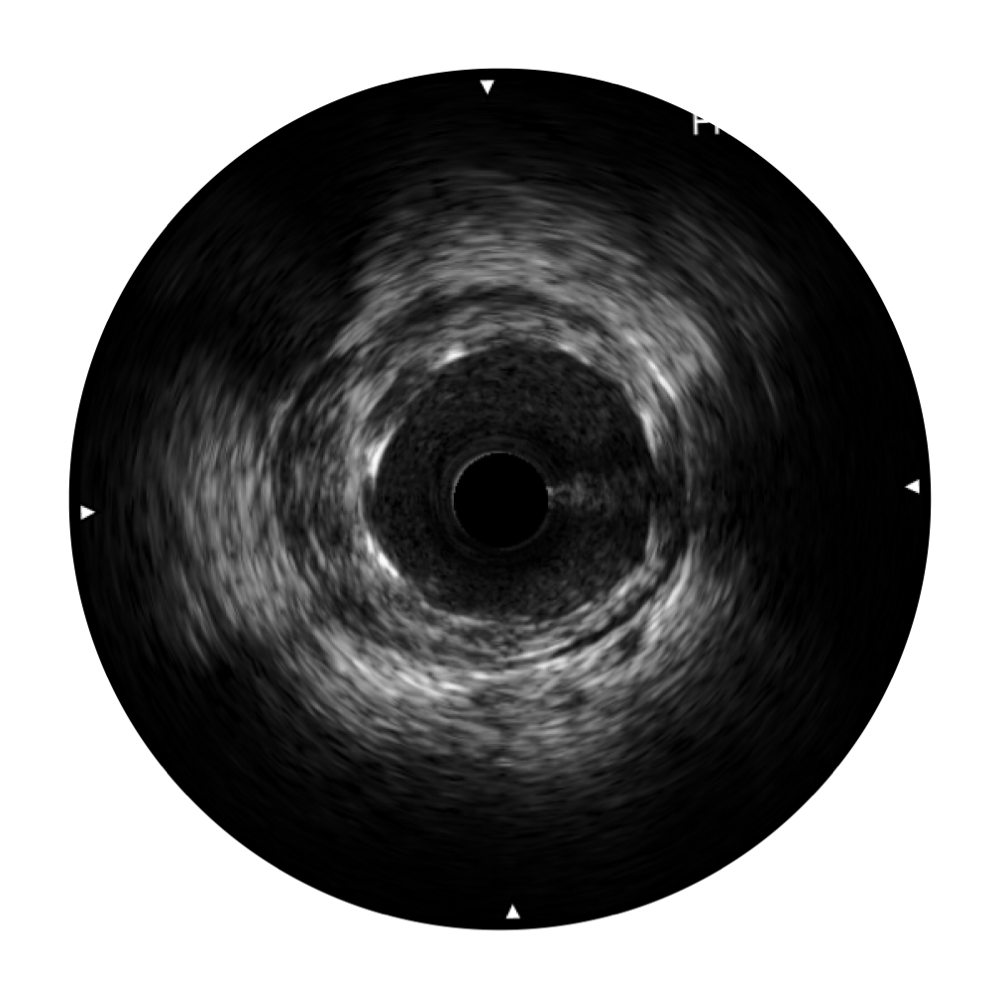

• 云顶集团官网宽频IVUS图像

• 传统IVUS图像

对比传统IVUS导管成像,云顶集团官网宽频IVUS图像的近场支架梁显影更细腻,远场中膜外血管仍清晰可辨,兼顾远中近,兼顾分辨力与穿透深度